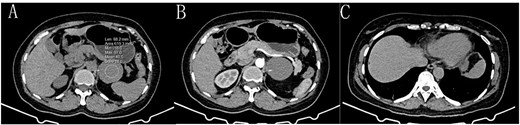

A 53-year-old female presented with intermittent upper abdominal distension and pain, accompanied by radiating pain in the lower back. She denied experiencing diarrhea, nausea, vomiting, black stools, or bloody stools. There were no symptoms of chills, fever, chest tightness, shortness of breath, palpitations, or dizziness. One day later, she sought treatment at the Emergency Department of the First Affiliated Hospital of Dali University. The patient had a history of angina pectoris for over six months and had been on long-term oral medications, including atorvastatin, metoprolol, and aspirin. She had no history of other gastrointestinal diseases and denied any other chronic illnesses, infectious diseases, trauma, surgery, or family history. She is married with children of an appropriate age. A thorough physical examination was performed. Her vital signs were stable, with no apparent abnormalities in the cardiopulmonary assessment. The abdomen was flat and soft, with no visible gastrointestinal or peristaltic waves. Palpation revealed tenderness in the upper abdomen, without rebound pain or palpable abdominal mass. Abdominal percussion and auscultation showed no obvious abnormalities. An emergency CT scan of the upper and middle abdomen revealed: [1] an undetermined soft tissue mass in front of the left kidney, [2] a small fat density focus (10 × 6 mm) beneath the capsule of the right lower lobe of the liver, and [3] possible cholecystitis with stones. An emergency hepatobiliary, pancreatic, and spleen ultrasound revealed a cystic mass in the retroperitoneal pancreatic tail (suggestive of a pancreatic cyst). Symptomatic treatment, including pain relief, was provided in the outpatient department, but the patient’s symptoms showed no significant improvement. She was subsequently admitted to the hospital due to a suspected pancreatic space-occupying lesion, possibly a pancreatic cyst. After admission, she underwent further auxiliary examinations. Results indicated a hypersensitivity C-reactive protein level greater than 10 mg/L, a white blood cell count of 12.76 × 109/L, and a neutrophil percentage of 82.2%. No significant abnormalities were found in routine urine analysis, liver and kidney function tests, electrolytes, infectious disease screening, or coagulation function. An enhanced CT scan of the upper and middle abdomen revealed a round soft tissue density shadow in the left retroperitoneum, measuring approximately 5.1 × 5.5 cm, with clear boundaries. The enhanced scan showed no enhancement. The tail of the pancreas was slightly compressed, and the left adrenal gland was compressed and displaced (Fig. 1). The radiologist suggested the presence of a left retroperitoneal mass, of undetermined nature, and gallbladder plication. Based on the patient’s medical history and auxiliary examinations, and after a discussion of the condition, a comprehensive diagnosis was made, including: (1) left retroperitoneal mass (possibly a pancreatic cyst), (2) gallbladder stones with chronic cholecystitis, and (3) coronary atherosclerotic heart disease. Following consultation with the family, it was decided that the patient would undergo mass resection surgery on the third day after admission.

A: Gastric bronchogenic cyst on a plain CT scan (→), with a CT value of approximately 40.5 HU. B: The CT-enhanced arterial phase shows no enhancement of the cyst (→). C: A postoperative plain CT scan shows that the cyst has been successfully removed.

During surgery, a lump was identified behind the tail of the pancreatic body, with no apparent adhesion or invasion of the surrounding area. The pancreatic tail was completely freed and suspended along with the splenic artery and vein, revealing that the mass originated from the lesser curvature of the stomach (Fig. 2). After fully dissociating the mass, the gastric tissue was separated from it along the lesser curvature, and the mass was completely removed from the surface of the left renal vein. The mass, visible to the naked eye, measured approximately 5 × 6 cm (Fig. 3), and yellow viscous content was observed upon incision. Postoperative pathological examination revealed a retroperitoneal mass. The fibrous cyst wall tissue was lined with ciliated columnar epithelium, with numerous foam cells and lymphocyte infiltration, suggesting a diagnosis of bronchogenic cyst (Fig. 3). The postoperative diagnosis included gastric bronchogenic cyst, gallbladder stones with chronic cholecystitis, and coronary atherosclerotic heart disease. The patient received postoperative symptomatic treatment, including antiinfection therapy and fluid replacement. A follow-up abdominal CT scan six days after surgery showed no obvious residual cysts (Fig. 1C), and the patient was discharged.

It is challenging to make a definitive diagnosis of gastric bronchogenic cyst before surgery, though imaging can assist in the process. On CT, bronchogenic cysts typically appear as unilocular, ovate lesions with well-circumscribed smooth, or lobulated borders. They are usually described as homogenous hypoattenuating lesions without enhancement, and calcification may sometimes be present in the cyst wall [7]. In this case, the cyst had a CT value of 40.5 HU, slightly lower than that of the liver, and ultrasound indicated cystic imaging. Gastric bronchogenic cysts must be differentiated from other conditions such as cystic lymphoma, cystic mesothelioma, cystic teratoma, gastrointestinal cysts, gastrointestinal stromal tumors, adrenal tumors, and pancreatic tumors. Histopathological examination is necessary to confirm the diagnosis of bronchogenic cyst. These cysts are characterized by a lining of respiratory tissue, ciliated cuboidal, or columnar epithelium, which may be pseudostratified, and contain thick, mucoid material secreted from this lining. Goblet cells, lymphoid aggregates, glands, and/or cartilage may also be associated with the respiratory epithelium [8]. In this case, the patient had a unique anatomical feature, with the cyst located at the tail of the pancreatic body. It is critical during surgery to completely free the pancreatic body and tail, while carefully protecting the splenic and left renal veins from potential damage. The bronchogenic cyst developed near the lesser curvature of the stomach, close to the pancreatic tail. If the tail of the pancreas is not fully released during surgery, there is a risk of misdiagnosis as a mass of the pancreatic tail, which could lead to unnecessary pancreatectomy and splenectomy. This could result in the unnecessary removal of vital organs, placing a significant physical and financial burden on the patient. To avoid such outcomes, subjective judgments should be avoided during surgery. Instead, the surrounding tissues should be completely freed, and a thorough search should be conducted to identify the cyst’s source. This approach can help preserve vital organs and ensure complete removal of the lesion.